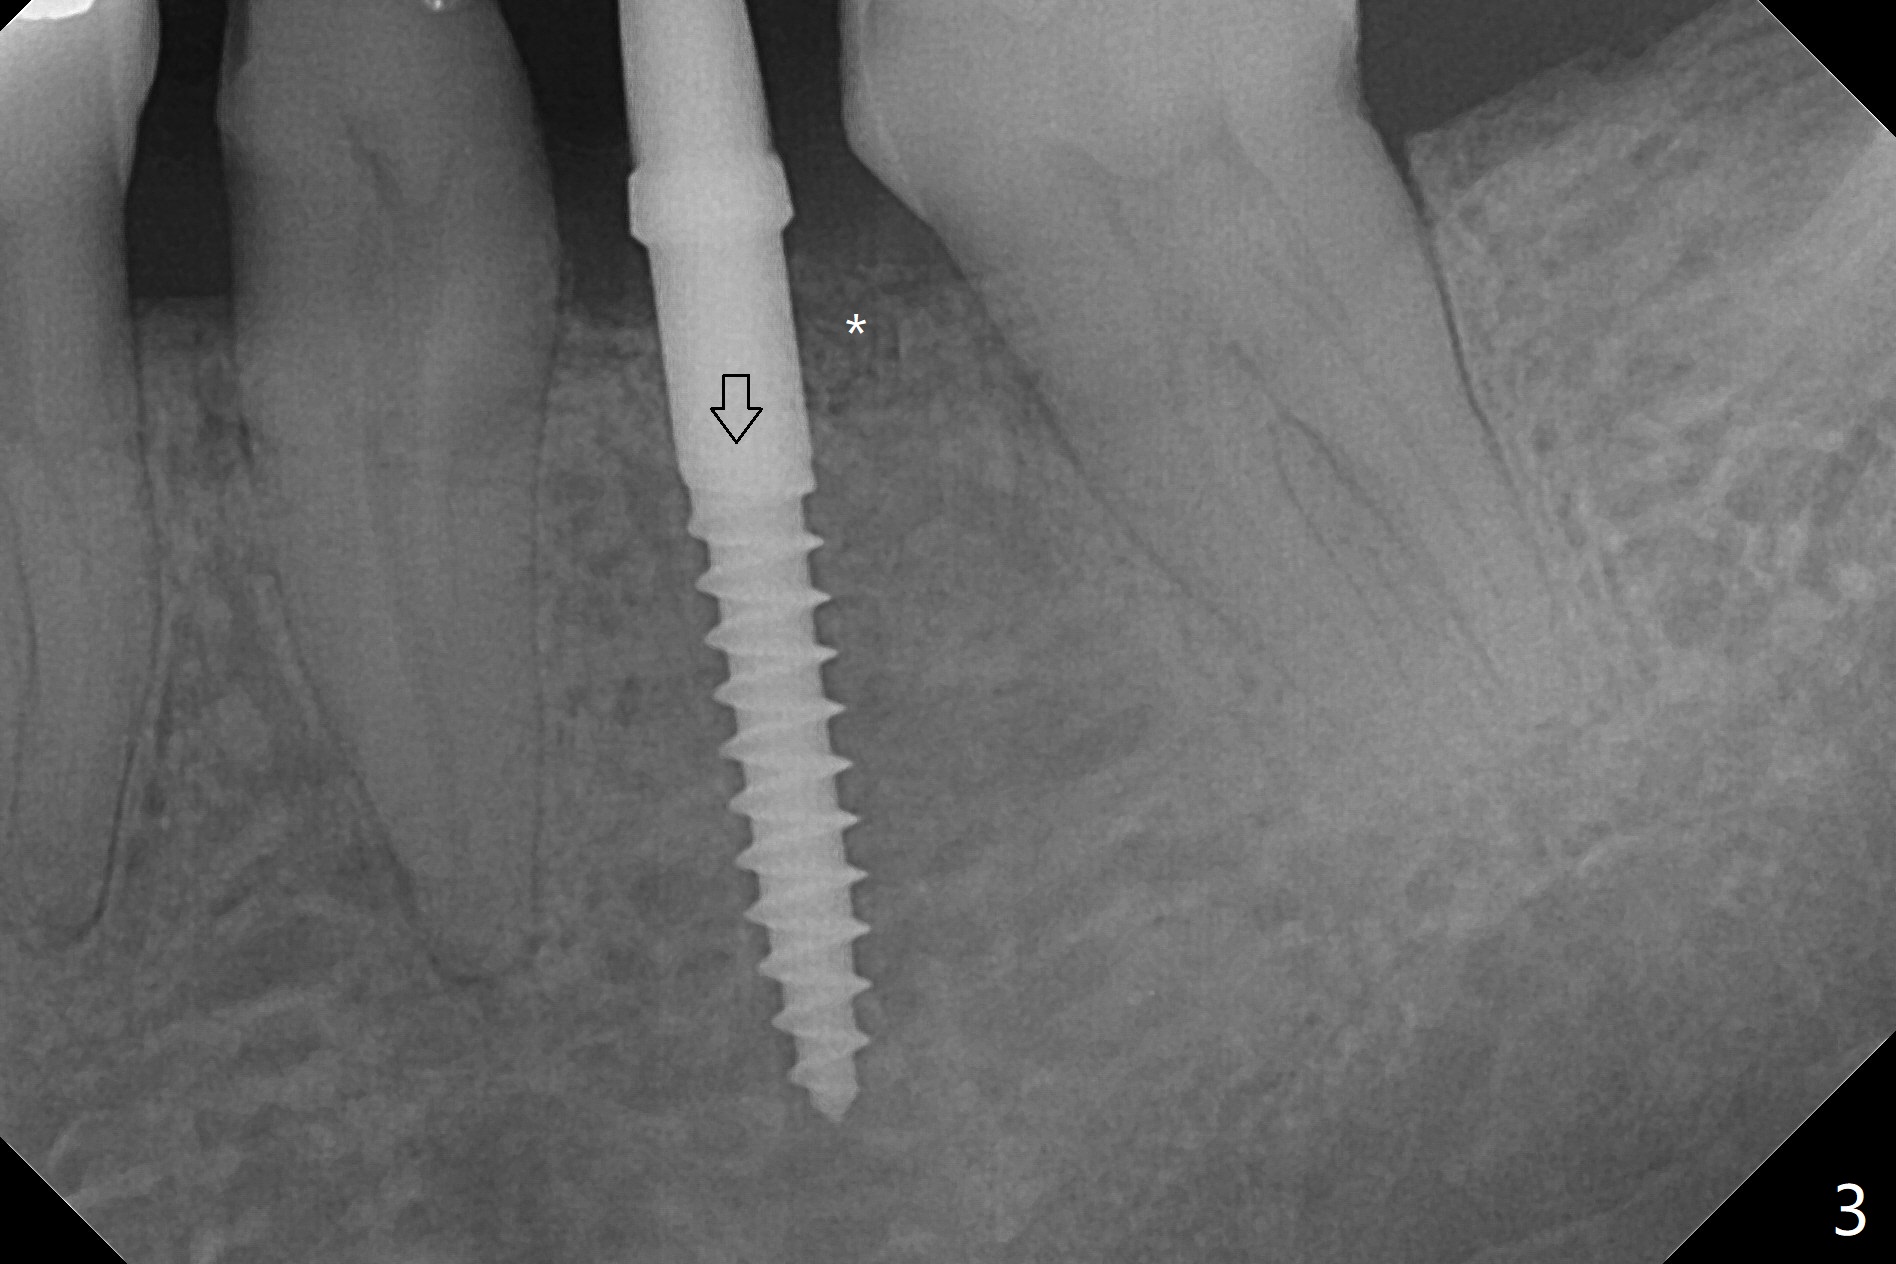

To start osteotomy in the narrow ridge with the oblique top, the latter needs to be trimmed at #19. It would be less traumatic to have a narrow bone trimmer (e.g., 3 mm) in the Narrow Guide Kit. This case is originally designed to have ridge split. The ridge top is trimmed with surgical handpiece after incision. Following pointed drill, the cylindrical part of the 2.2x8.5 mm drill cannot engage to the metal sleeve with 10.5 mm offset. The guide has to be removed. The first 1-2 mm osteotomy has to be done free hand before reuse of the guide and the drill. Nevertheless, the osteotomy is precise buccolingual when it is finished (Fig.1). If the short drill (2.2x7.3 mm) cannot be produced, the next case should have 12 mm offset for narrow guide and an additional guide with regular metal sleeve for tissue punch and bone trimmer. Since the mesiodistal space is also limited, a 2.5x12(4) mm 1-piece implant is placed instead (Fig.2). With the implant placed a little deeper (Fig.3 arrow), bone graft is placed (*), followed by suture. When the procedure is done, the patient is tired. It would be nice to have a more complete Narrow Guide Kit with its own bone trimmer and 2.2x7.3 mm drill. There is no bone loss with retention of bone graft 4 months postop; after reprep of the neighboring teeth, impression is taken (Fig.4). The three crowns are cemented 4.5 months postop (Fig.5).